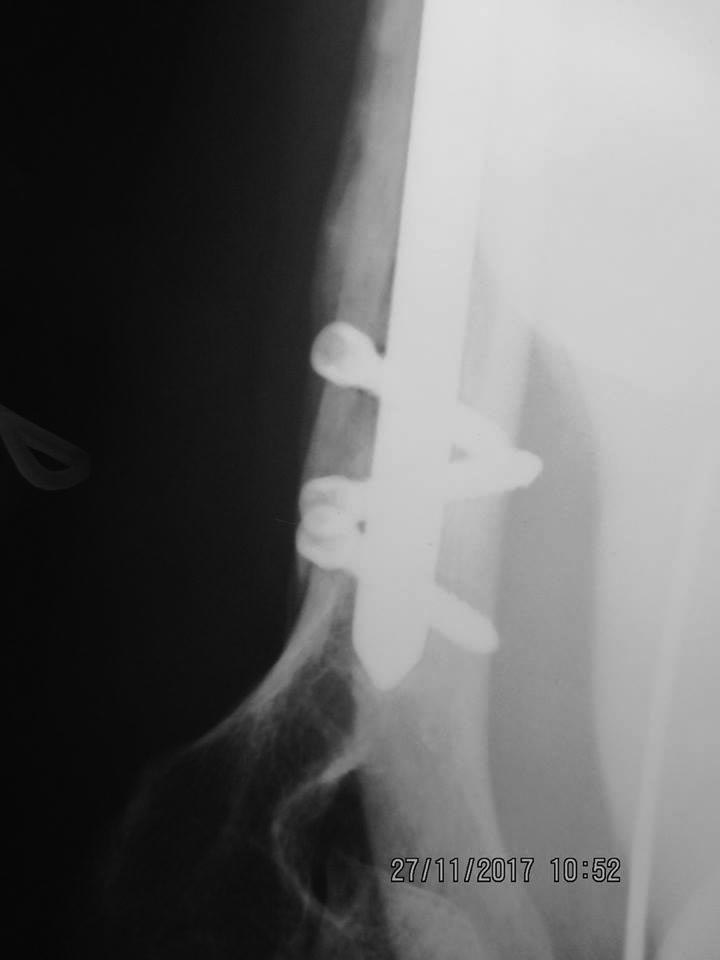

Пациентка 47 лет; травма – 15.07.17, операция – 24.07.17. В результате реабилитационного лечения: отведение - 45 гр., сгибание -75 гр.

Импиджмент. Глубже нужно было вводить. Возможно есть проблемы с сухожилием надостной

Точка введения оччччень латеральная. Откуда и проблемы.

Отправитель: Alexander Chelnokov 28 Ноябрь 2017, 03:32

Качество фото не позволяет. Видно суставные концы, а между ними засветка